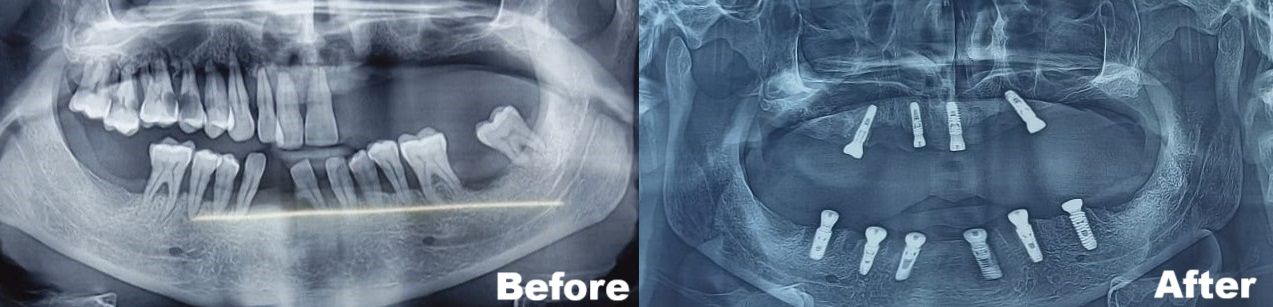

This article reports the full mouth rehabilitation of a 45-year-old male patient with chronic generalized periodontitis and grade 3 mobile upper and lower teeth. In CBCT, there was only 4-5 mm bone below both sides of the maxillary sinus. We at Magadh Oro Dental decided to extract all teeth and place 6 implants in the lower arch and 4 implants in the upper arch followed by the placement of temporary dentures during the osseointegration period.